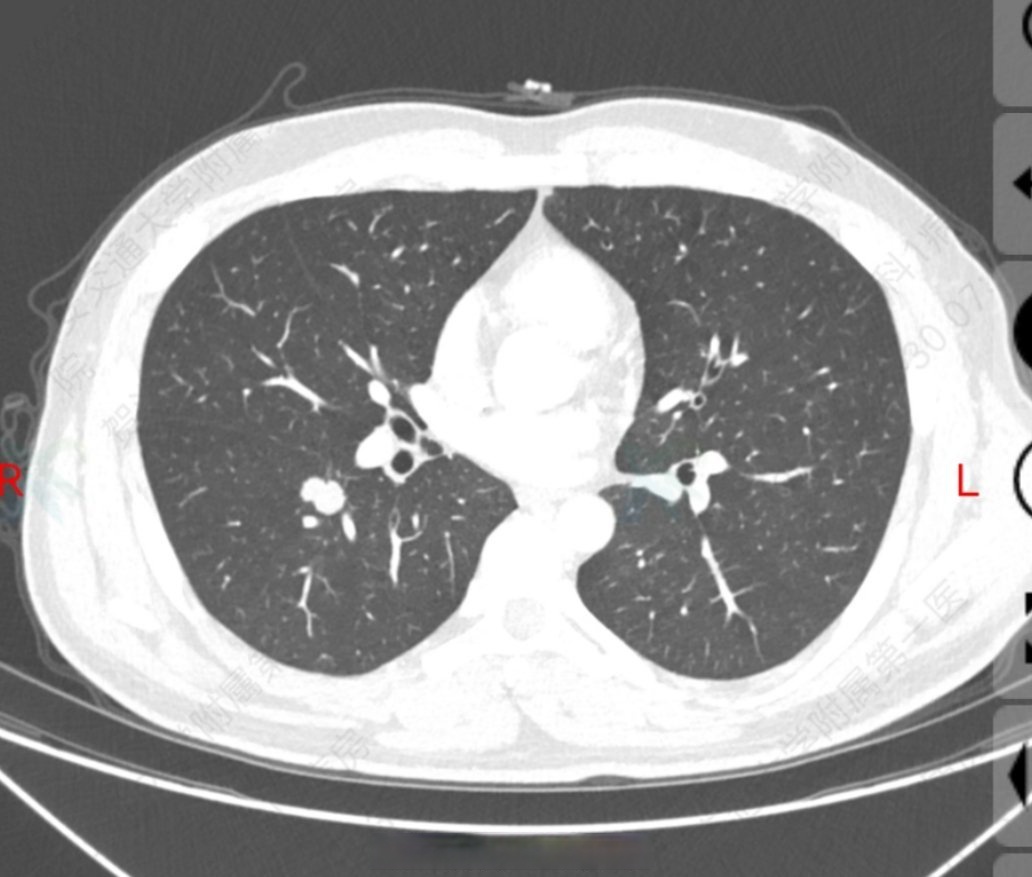

肺部结节几年能活多久

对于发现时已经是晚期的患者,经过手术联合术后放化疗,其5年生存率可以达到40%80%此外,建议肺结节患者每年进行体检,检查胸片可以及早发现肺部结节等病变,进而采取及时准确的治疗,以减少对寿命的影响。...